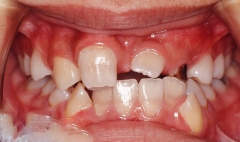

治療前 正面

乱杭歯になっています